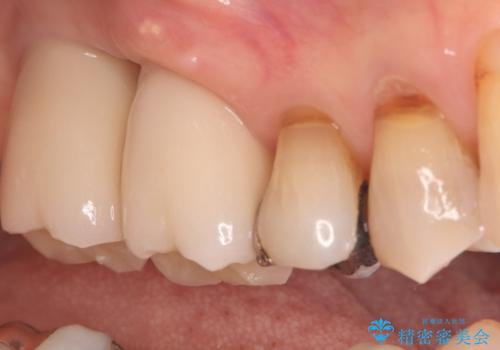

今回の治療では、まず重度歯周病の右上6番を慎重に抜歯し、その直後に6番と、すでに欠損していた7番の部分に、合わせて2本のインプラントを埋入しました。

抜歯即時埋入(6番): 抜歯と同時にインプラントを埋入することで、骨の吸収を最小限に抑え、治療期間を大幅に短縮しました。

7番のインプラント埋入: 6番と同時に埋入することで、治癒期間を一括で管理でき、効率的に治療を進めることができました。

その後、インプラントと骨がしっかりと結合するのを待ってから、最終的な被せ物(クラウン)を装着。これにより、重度歯周病で失われた2本の奥歯を、強固で安定したインプラントで再建。以前のような不安なく、しっかりと噛める快適な食生活を取り戻していただけました。